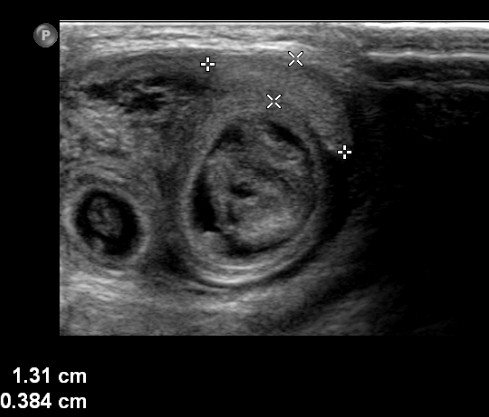

On initial evaluation he appeared nontoxic. Abdominal exam showed mild distension and possible guarding. Genitourinary exam revealed a non-tender, swollen right hemiscrotum that transilluminated, and a palpable right testicle. Given the concerning abdominal exam, a scrotal ultrasound was performed which showed loops of bowel, a hydrocele, and a right testicle with poor flow (Figure 1). After manual reduction was unsuccessful by the emergency physician and pediatric surgeon, the patient was urgently taken to the operating room. During laparotomy 10 centimeters of ischemic bowel was reduced and immediately regained perfusion. An ischemic testicle was also identified but not removed. Postoperatively, the patient was observed in the intensive care unit and was discharged on day four without complication.

| Figure 1. |